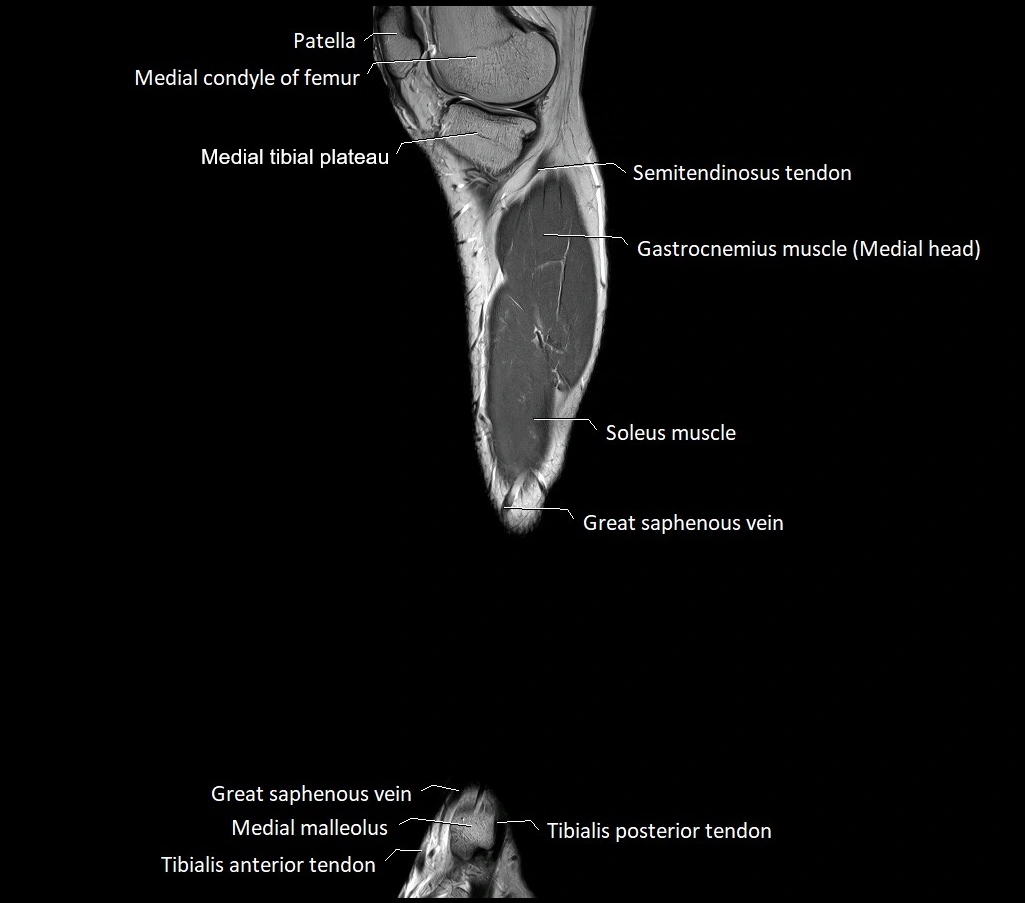

MRI image